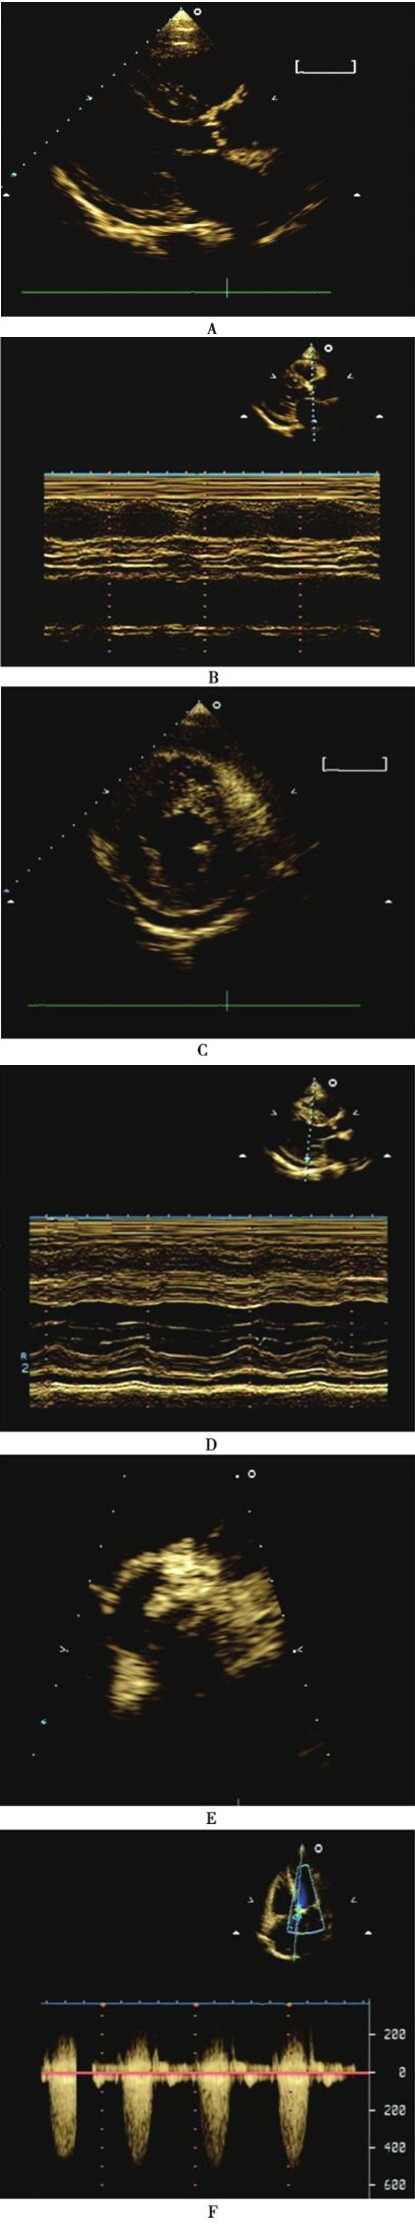

超声心动图:双心房增大,左心室壁增厚;主动脉瓣重度钙化,瓣叶结构显示不清,重度狭窄;二尖瓣后叶瓣环钙化,少量反流;少量心包积液;未见明显节段性室壁运动异常,左心室射血分数58%。(图63-1)。

图63-1 超声心动图

A:二维超声心动图左心室长轴切面示室间隔、左心室后壁增厚,主动脉瓣增厚、回声增强,少量心包积液;B:M型超声心动图左心室长轴切面示主动脉瓣开放幅度减小;C:二维超声心动图乳头肌水平短轴切面示左心室壁增厚、少量心包积液;D:M型超声心动图左室长轴切面腱索水平示左心室壁增厚、少量心包积液;E:二维超声心动图大动脉水平短轴切面示主动脉瓣严重钙化、狭窄;F:连续多普勒心尖五腔心切面示主动脉瓣前向流速显著增快